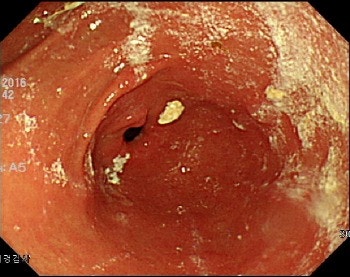

그래서 오늘은 내시경 전의 주의사항이나 특정 약 복용은 괜찮은지 등에 대해 이야기하고자 합니다.내시경 검사란?내시경으로 신체의 다양한 내강을 관찰, 검사함으로써 검사가 필요한 장기에 내시경을 삽입하고 기체나 액체로 내강을 부풀리면서 장기의 구조와 상태를 파악하는 검사 방법입니다.

수술로 몸을 절개하지 않아도 눈으로 조직의 병변을 확인할 수 있다는 장점이 있습니다.

내시경 검사로 단순한 염증성 질환부터 친정, 암, 용종 등 다양한 질환을 판단할 수 있습니다.